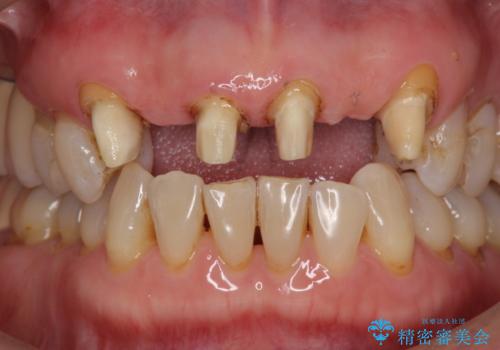

不自然な前歯ブリッジ ジルコニアブリッジによるやり替え

- 20年前に入れたブリッジの見た目の改善を求めて来院されました。

丁寧に現在装着されているブリッジを除去後、精度の高いジルコニアブリッジで審美性の改善を計画します。

- 66万円(仮歯・ジルコニアクラウン×6)費用は治療当時の料金となります

前歯に限らず拡大鏡を用いた精密な形成・シリコンを用いた精度の高い印象を徹底することで治療全体の質を高め、審美性だけでなく長期的な予後を期待することができます。